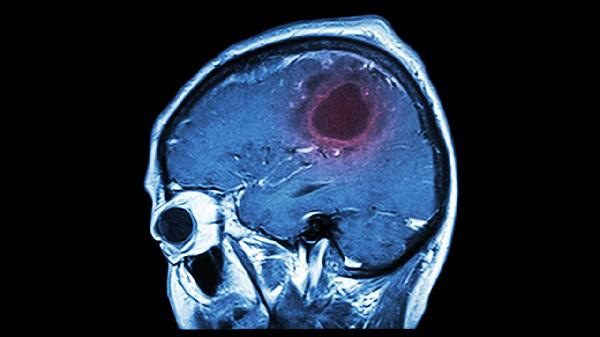

大脑栓塞患者除针灸外,应坚持服用阿司匹林肠溶片、硫酸氢氯吡格雷片等抗血小板药物,配合肢体功能锻炼和语言康复训练。饮食上注意低盐低脂,控制血压血糖,避免情绪激动和过度劳累。定期复查头颅CT或MRI,监测病情变化。若出现肢体无力加重、言语不清等新发症状,须立即就医。